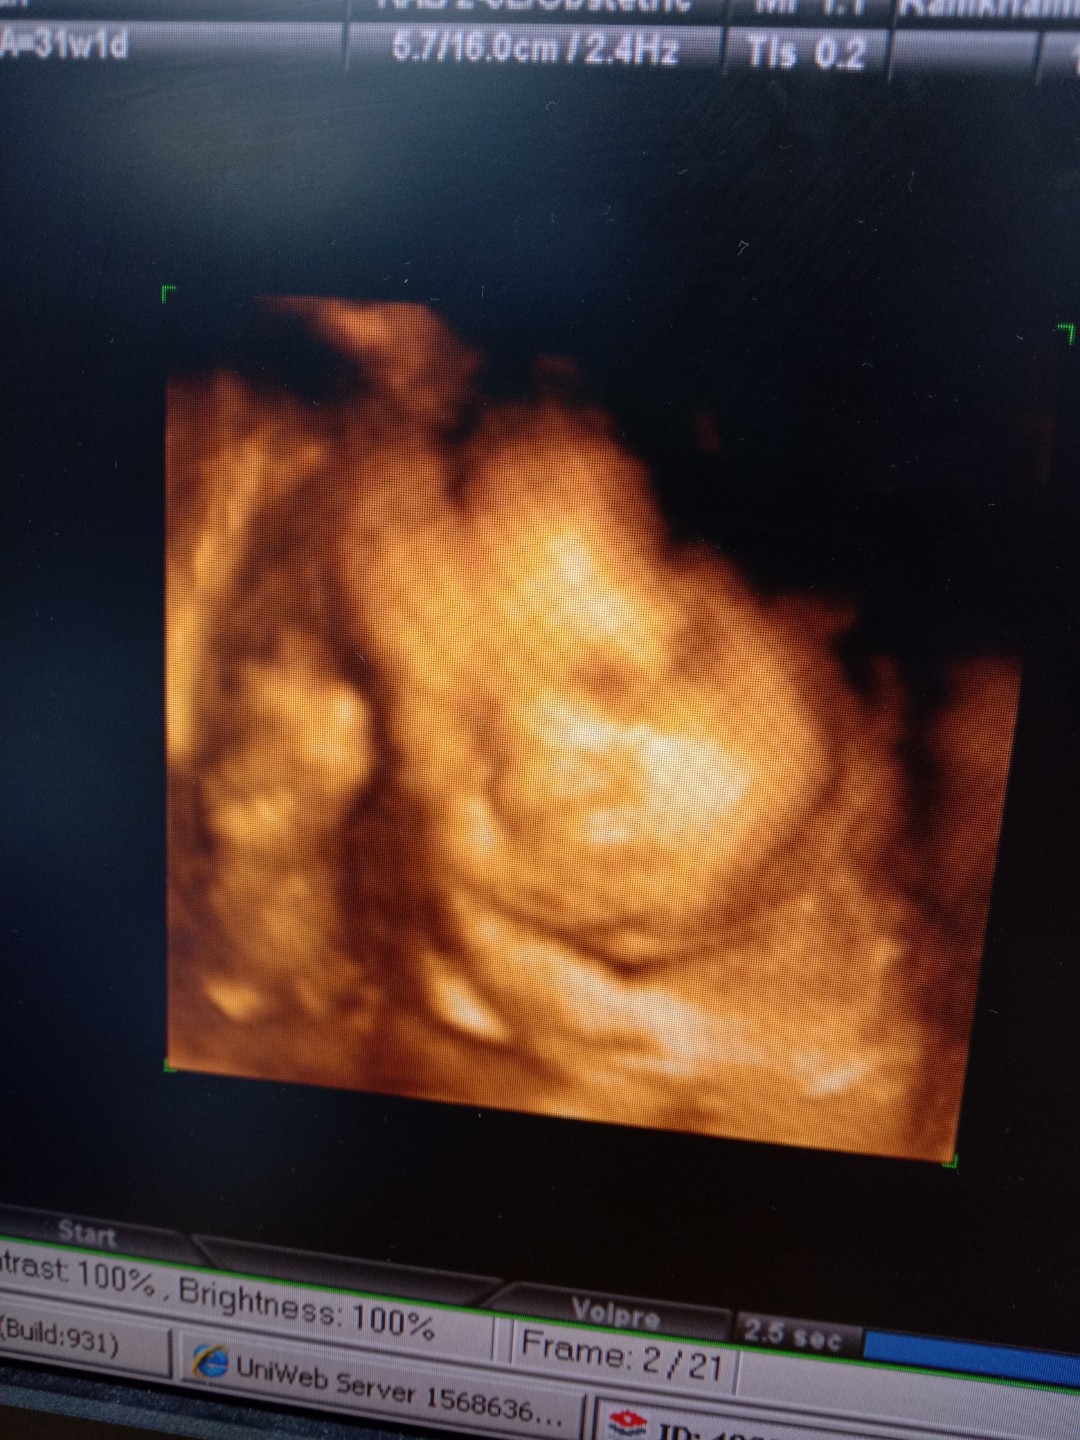

เอาเด็กชายปากคว่ำ เดือน พย. มาอวดจ้า

อายุครรถ์ 32วีค5วัน ผมหนัก 2,100 แล้วครับ ขอดูเด็กเดือน พย. น่ารักๆหน่อยครับ ผมไม่ชอบเลยเวลาคุณหมอซาวด์ หน้าจะบึ้งหน่อยๆ55555